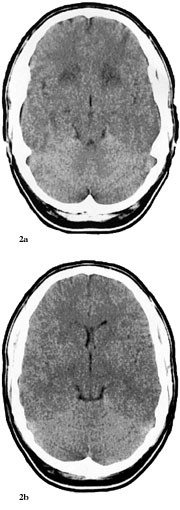

Pasienten ble overflyttet til Namdal Sykehus 6.6. Han var somnolent, desorientert og gav stereotype svar. Han hadde ingen fokale utfall. På mistanke om herpes simplex-encefalitt ble det iverksatt behandling med aciklovir 3 ⋅ 750 mg intravenøst, i tillegg fenytoin 2 ⋅ 250 mg intravenøst mot symptomatiske epileptiske anfall. Dagen etter ble pasienten soporøs. EEG var preget av en generalisert langsom aktivitet, delvis i form av bilateral synkron, rytmisk deltaaktivitet (frontal intermittent rhythmic delta acitvity, FIRDA). CT viste symmetriske forandringer i basalgangliene og basale deler av cerebrum som var ødematøs (fig 2a, 2b). En ny spinalvæskeprøve, tatt 8.6., viste 17 celler. En CT fra 9.6. viste progredierende forandringer (fig 3).

Dessverre hadde vi ingen mulighet til å få utført MR og obduksjon. Likevel er en akutt demyeliniserende encefalomyelitt mindre sannsynlig på grunn av at sykdomsutviklingen ikke kom helt akutt, men var gradvis innsettende i løpet av ti dager. Dessuten hadde man ikke fokale eller multifokale motoriske eller sensible utfall (10, 13). CT-funn viste progredierende, symmetriske forandringer som gav hypodensitet først i basalganglier og senere generelt, men hele tiden mest i basale deler av storehjernen og i de limbiske strukturer (fig 1 – 3). Retrospektivt aner man allerede ved første CT-undersøkelse (fig 1b) små hypodense områder ut for 3. ventrikkel på hver side lavt i basalgangliene. Disse funnene tyder heller på en atypisk encefalitt enn på en akutt demyeliniserende encefalomyelitt og korresponderer med de kliniske funn av hukommelsesproblemer og personlighetsforandringer. Pasienten fikk terminalt sentral respirasjonsstans, noe som kan tyde på hjernestammeaffeksjon.